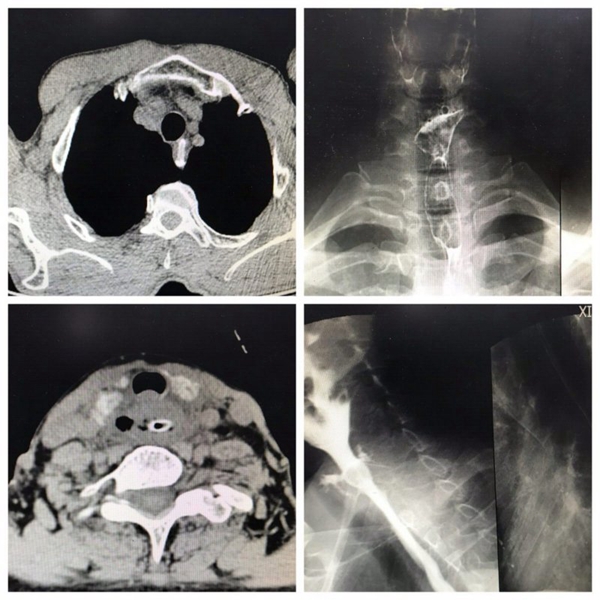

作为中国人的传统节日,吃粽子、赛龙舟是端午节的必备项目。然而,粽子好吃,里面的枣核却有可能惹出大麻烦。仅仅小长假第一天,……